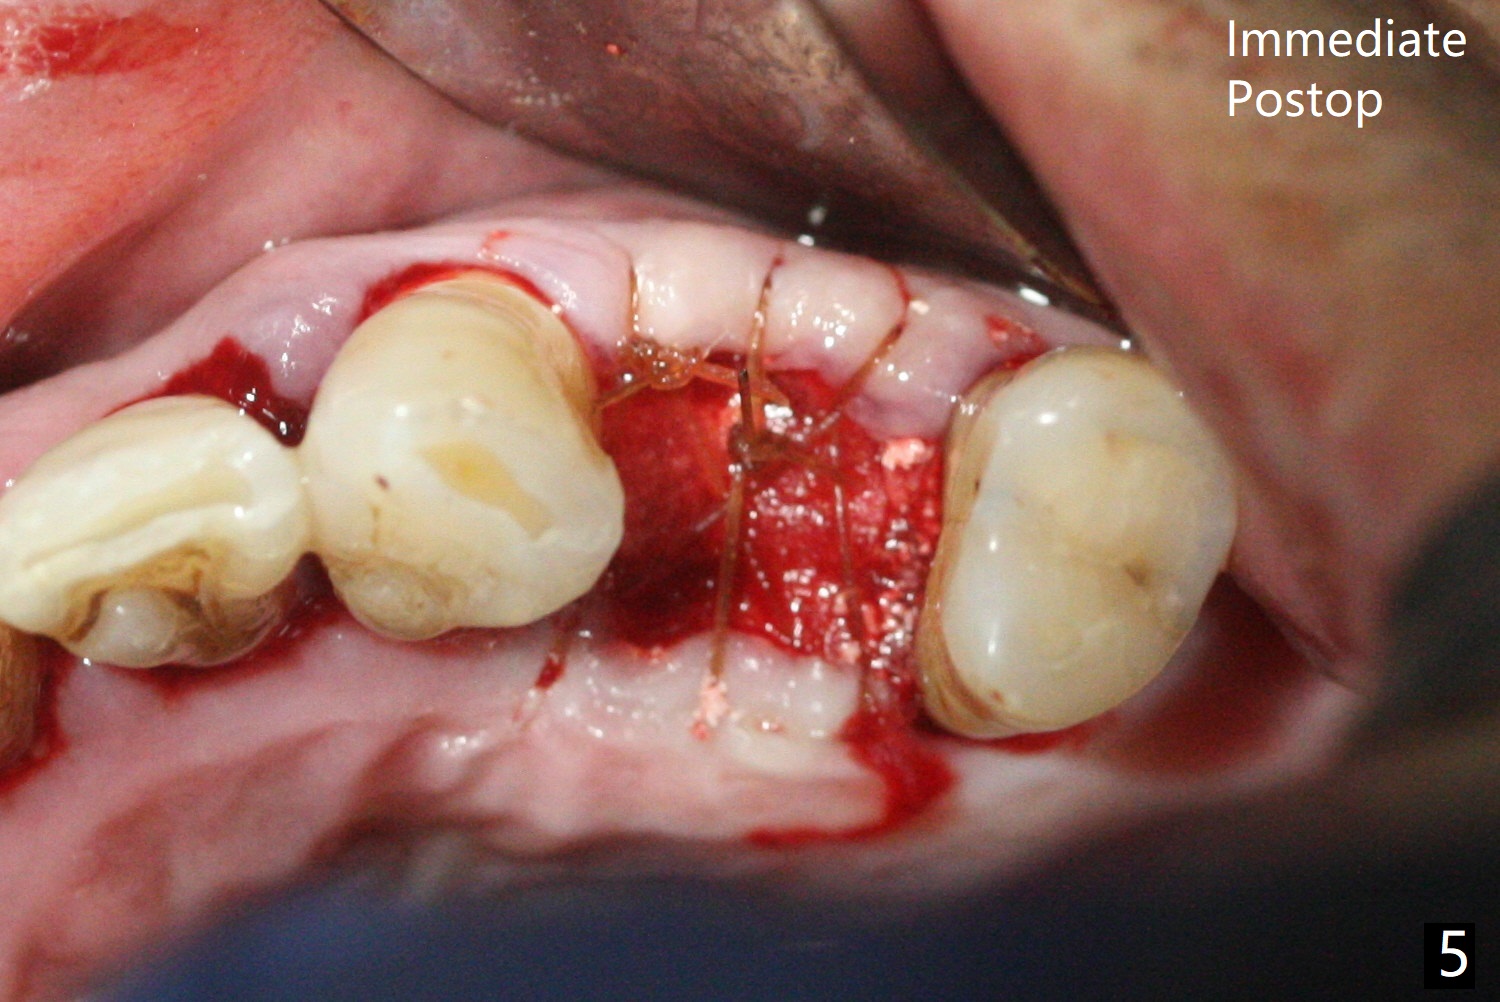

58岁男,吸烟,要求拔除断裂左上4(图一,二),邻牙(5)骨质吸收严重(图一,四),右上4,5拔除后骨质吸收(图一),所以左上4拔除(图三)位点保留(图四:人工骨,图五:GEM Cap)重要,尽管他准备做假牙。

今天手术缺点局麻不足,出血控制不好。明天一早同样病例,左上4拔除,使用两只局麻药(红,绿),准备小纱布塞入牙槽窝止血,植骨前才取出纱布,并且应用骨粉充填器。如果GEM bone matrix没有,使用另外一种人工骨。同样使用GEM Cap覆盖骨粉,利用牙周胶水固定。Return to No Caries Plug Xin Wei, DDS, PhD, MS 1st edition 11/06/2020, last revision 11/06/2020